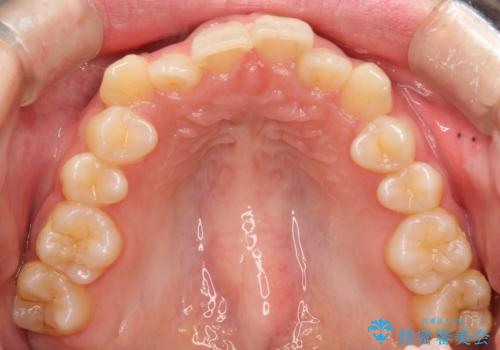

- 前歯のガタガタを主訴に来院された患者様です。

八重歯になっており、下顎の前歯が上顎の前歯に隠れてしまう、ディープバイトという状態でした。

インビザラインを使用して矯正する計画としました。

ディープバイトの場合、ワイヤー装置の装着が難しいことがあります。

インビザラインではかみ合わせに左右されず装着できるメリットがあり、ワイヤーに比べインビザラインの方が治療しやすい場合もあります。